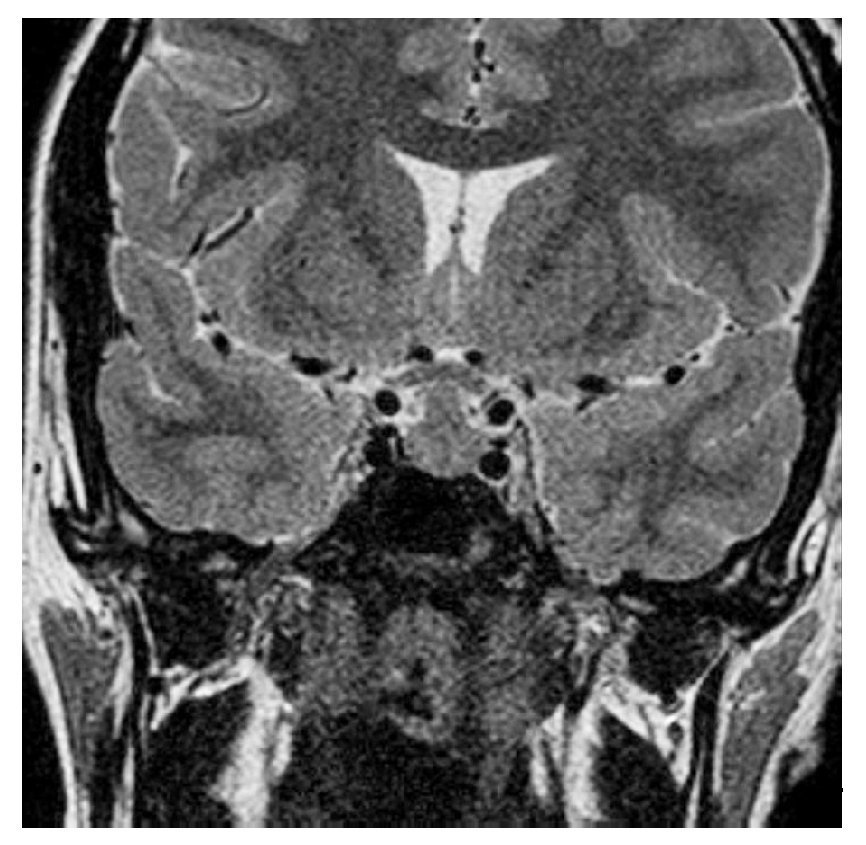

Paciente varón de 14 años de edad, con talla baja y panhipopituitarismo.

Fig. 3.